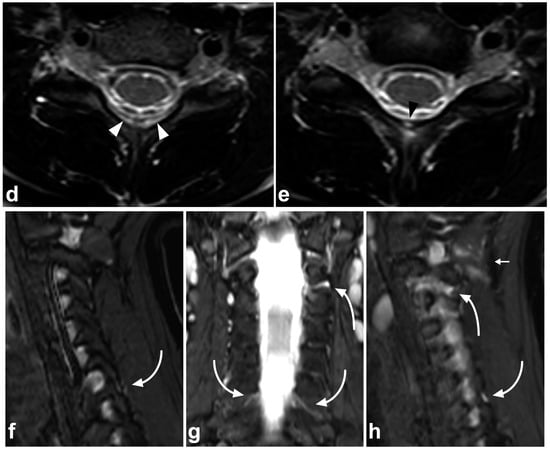

6. Spinal Cord Injuries

The use of MRI in acute spinal cord trauma was first described in 1983 [60,61] and it has been the gold standard in imaging these injuries ever since. T1-weighted, T2-weighted, and STIR sequences are the cornerstones in assessing the cord [49]. Diffusion-weighted imaging (DWI) and diffusion tensor imaging (DTI) might be useful in detecting subtle injuries and as a prognostic biomarker, but their role in clinical practice is not fully established yet [62,63,64,65,66]. Susceptibility-weighted imaging (SWI) or T2*-weighted sequences might increase the sensitivity in the case of small intramedullary hemorrhages but are technically challenging to obtain due to pulsation and motion artifacts [67,68]. Cases of spinal cord injuries are presented in Figure 15 and Figure 16.

Figure 15.

(a) Sagittal T2-weighted. (b) Sagittal T1-weighted. (c) Sagittal T2-weighted fast field echo. (d) Coronal STIR. (e) Axial T2-weighted, level of the lower end plate of C6 (caudal dotted line in the image (b)). (f) Axial T1-weighted, level of the lower end plate of C6 (caudal dotted line in the image (b)). (g) Axial T2-weighted, level of the lower end plate of C5 (cranial dotted line in the image (b)). (h) Axial T1-weighted, level of the lower end plate of C5 (cranial dotted line in the image (b)). A 17-year-old male after diving into shallow water. The spinal cord is edematous approximately from the level of the lower end plate of C4 to the lower end plate of C6 (black arrowheads). There is a hemorrhagic contusion in the right-sided grey matter (white arrows) and a contusion without macroscopic hemorrhage on the left side (white arrowheads). Hematoma can be seen in the anterior epidural space (curved arrows). There are fractures of vertebral bodies and posterior arches of C5 and C6 (asterisks and small arrows).

Figure 16.

(a) Sagittal T2-weighted. (b) Coronal STIR. (c) Axial T2-weighted (dotted line in the image (a)). A 2-year-old female, severe cervical fracture–dislocation after a car accident. The spinal cord is transected. The cord caudally to the transection site (arrows) is dislocated posteriorly and on the right side of the cranial end of the transected cord (arrowhead). An extensive hematoma is seen around the fracture.